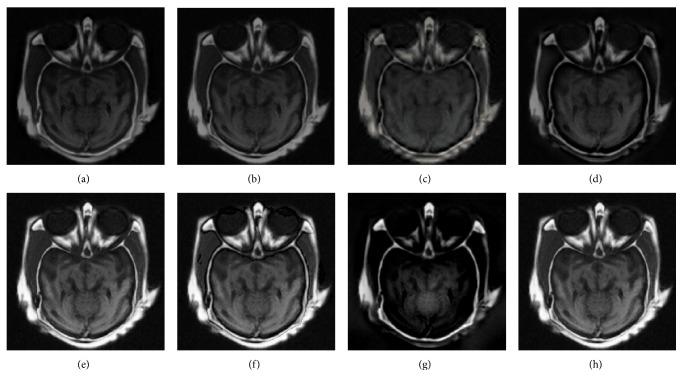

Medical image fusion plays an important role in diagnosis and treatment of diseases such as image-guided radiotherapy and surgery. Although numerous medical image fusion methods have been proposed, most of these approaches are sensitive to the noise and usually lead to fusion image distortion, and image information loss. Furthermore, they lack universality when dealing with different kinds of medical images. In this paper, we propose a new medical image fusion to overcome the aforementioned issues of the existing methods. It is achieved by combining with rolling guidance filter (RGF) and spiking cortical model (SCM). Firstly, saliency of medical images can be captured by RGF. Secondly, a self-adaptive threshold of SCM is gained by utilizing the mean and variance of the source images. Finally, fused image can be gotten by SCM motivated by RGF coefficients. Experimental results show that the proposed method is superior to other current popular ones in both subjectively visual performance and objective criteria.

医学图像融合在诸如图像引导放疗和手术等疾病的诊断和治疗中发挥着重要作用。尽管已经提出了许多医学图像融合方法,但这些方法大多对噪声敏感,通常会导致融合图像失真和图像信息丢失。此外,它们在处理不同类型的医学图像时缺乏通用性。在本文中,我们提出了一种新的医学图像融合方法来克服现有方法的上述问题。它是通过结合滚动引导滤波器(RGF)和脉冲皮层模型(SCM)实现的。首先,RGF可以捕捉医学图像的显著性。其次,利用源图像的均值和方差获得SCM的自适应阈值。最后,由RGF系数驱动的SCM可以得到融合图像。实验结果表明,该方法在主观视觉性能和客观标准方面均优于其他当前流行的方法。